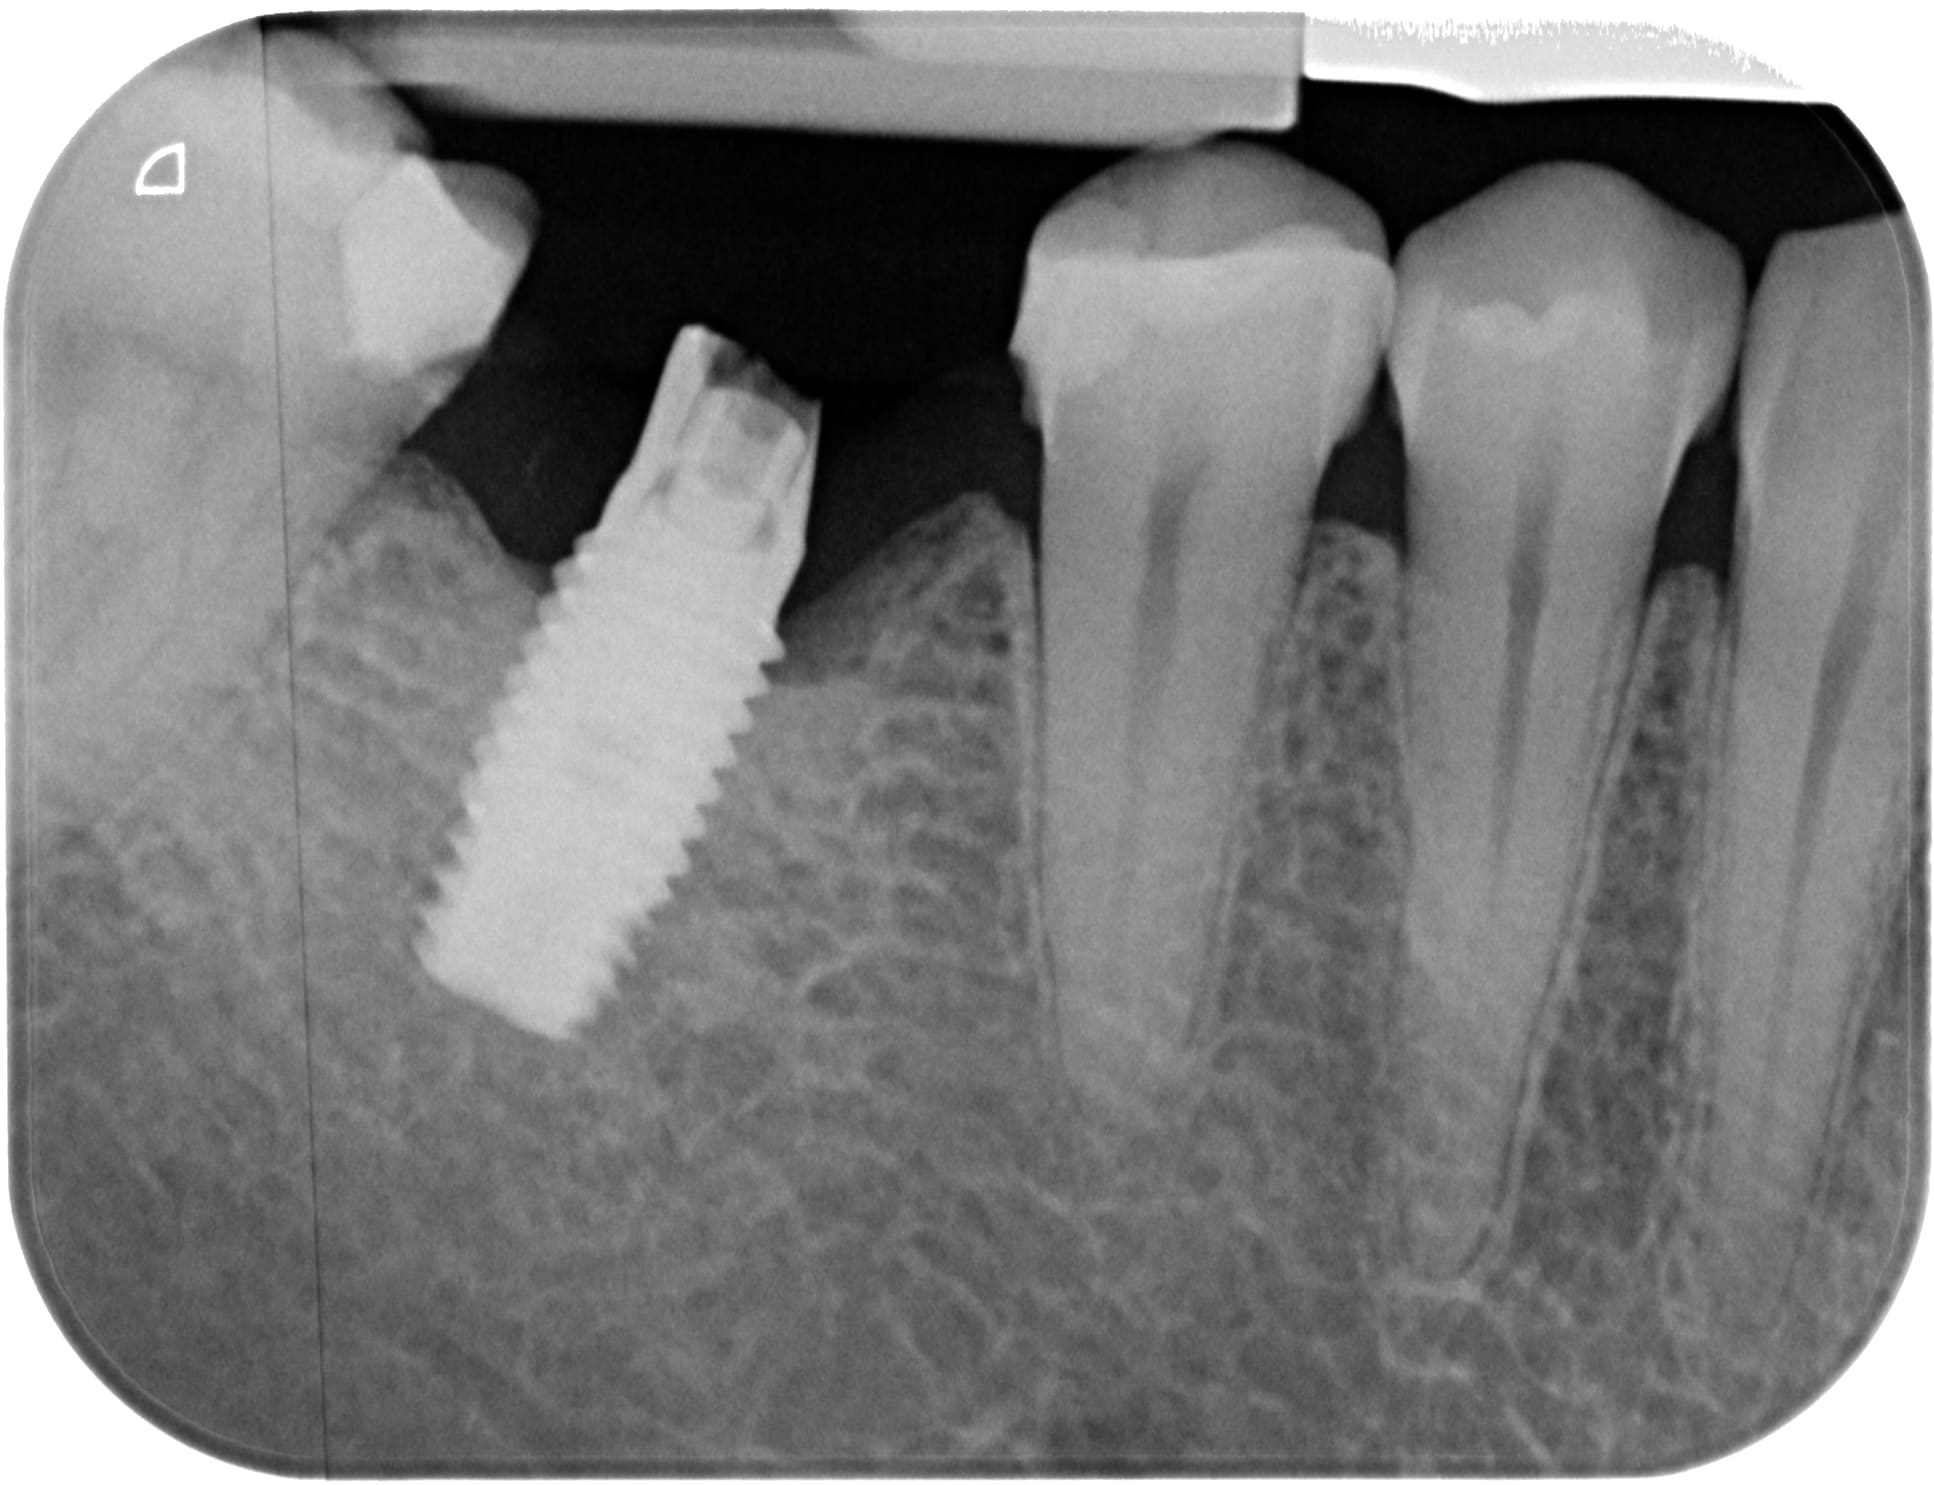

Je recherche une identification d'implant svp suite à fracture pilier.

Implant posé vers 2005 au COSEM Paris.